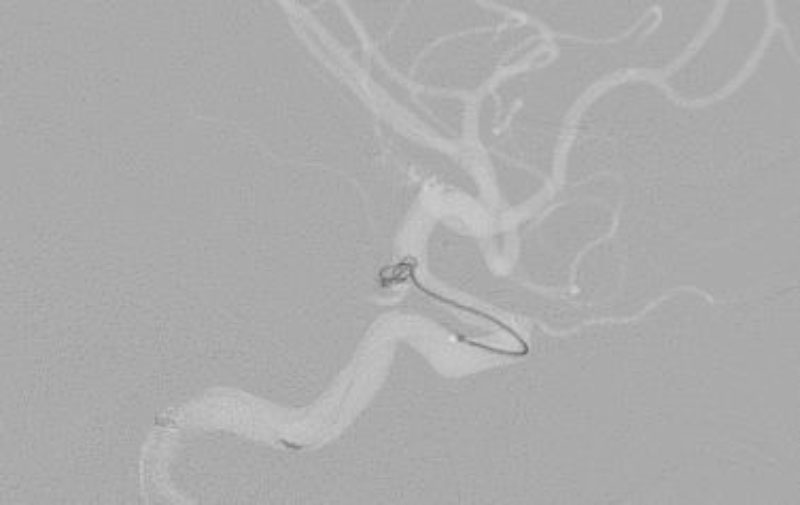

No.1631 手術中